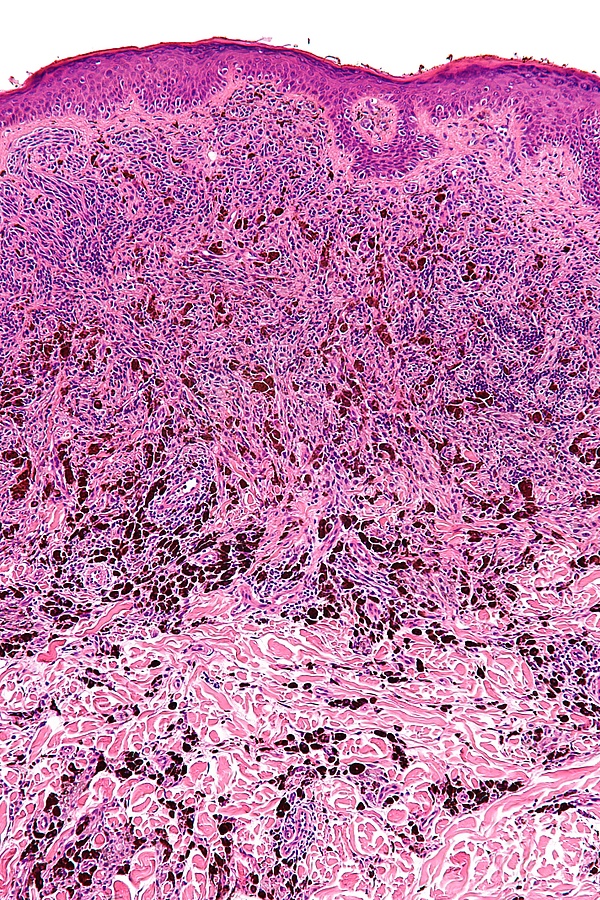

Основным методом подтверждения диагноза голубого невуса является гистологическое исследование биопсийного материала изменённого участка кожи. При простой форме выявляется узловатое скопление слабо пигментированных веретеновидных меланоцитов и выраженных дендритных меланоцитов, расположенных между утолщёнными коллагеновыми волокнами. Часто обнаруживаются меланофаги. Митотическая активность для этой формы нехарактерна[1][5]. Наблюдаются явления склероза в строме[9].

Клеточная форма представлена плотными фестончатыми скоплениями веретеновидных или овоидных меланоцитов, формирующих тяжи и гнёзда, которые могут распространяться в подкожно-жировую клетчатку. Для неё типично более выраженное клеточное строение при отсутствии выраженной цитологической атипии и некроза. Возможны редкие митозы. Часто определяется компонент простой формы внутри клеточного невуса[5].